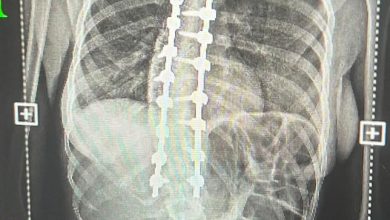

وبيّن البروفيسور الأغا أن تشخيص حالات قصر القامة يعتمد على إجراء مجموعة من الفحوصات والتحاليل الدقيقة، للتأكد من أن السبب الحقيقي يعود إلى نقص هرمون النمو، وليس لعوامل عضوية أو وراثية أو صحية أخرى ، وبعد التأكد من التشخيص، يبدأ العلاج بهرمون النمو وفق خطة طبية مدروسة، مع متابعة دقيقة لمعدلات الطول والتغيرات التي تطرأ خلال فترة العلاج.